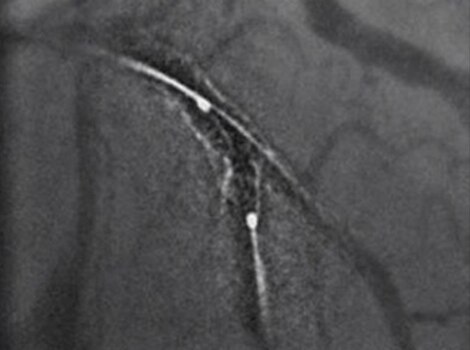

Intervention

For patients sent for revascularization in the catheterization lab, attempts are made to rapidly access the culprit artery and complete further assessment of coronary tree. Rapid intervention can help minimize time to reperfusion from first medical contact.

Innova IGS 5 or Discovery IGS 7

Helps reduce use of contrast and dose with one of the industry’s highest ratings for Detective Quantum Efficiency (DQE).12 Read More

PCI ASSIST13

Help plan, assess and guide interventional procedures with improved visibility up to 85 percent in moving anatomy. Read More

Successful PCI of the stenotic lesions involves planning, guidance, and assessment of the culprit lesion and assessment of the remainder of the coronary tree.

Innova IGS 55

Helps reduce use of contrast and dose with one of the industry’s highest ratings for Detective Quantum Efficiency (DQE).

Read More

PCI ASSIST6

Help plan, assess and guide interventional procedures with improved visibility up to 85 percent in moving anatomy.